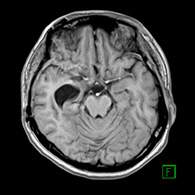

症例2) 38歳女性、左三叉神経鞘腫、外科治療のみ

< 画像所見 >

右三叉神経部に大きな腫瘍あり。

< 手術所見 >

ナビゲーションシステムの使用

< 術後画像所見 >